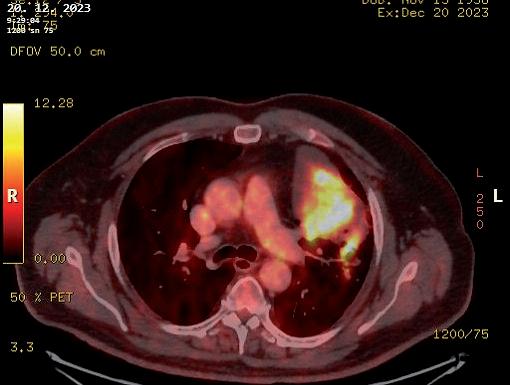

obr. 3.4 Adenokarcinom plicní po neoadjuvanci indikovaný k operačnímu řešení u 65letého muže na CT (a) a PET CT (b) obraze je masou nádoru natolik objemný (v největším rozměru prakticky 10 cm), že postihuje více než objem jednoho segmentu horního laloku levé plíce. Pro bezpečné vyjmutí resekátu nádoru, laloku plicního, je v tomto případě nutná regulérní torakotomie. Nádor dosahuje blízkosti odstupu tepenných větví pro horní lalok. Takový nález není vhodný pro videoskopické řešení. Výkon z torakotomie v takových případech upřednostníme. Po otevřené horní lobektomii vlevo a kompletní spádové lymfadenektomii nebylo patologem u pacienta nalezeno žádné nádorové postižení uzlin

uzlinách. Indikující chirurg je však často v situaci, kdy se primární ložisko v plíci podezřelé z maligního původu nezdařilo verifikovat bronchoskopií s biopsií nebo kar táčkovou cytologií, ani punkční transparietální biopsií pod CT (obr. 3.9, 3.10).

Na tomto místě je potřeba z praxe uvést, že výraz nou pomocí pro předoperační posouzení, jestli je nádor plíce zhoubný nebo nezhoubný, nemusí být ani PET CT [35, 36], které je v dnešní době jinak zásadním vyšet řením (obr. 3.11). Nevelké metabolicky aktivní ložisko i s aktivitou spádových uzlin může být počínající plicní malignitou, ale také zánětlivým procesem (obr. 3.12). Objemnější, asymptomatický, náhodně objevený, cent rálně v laloku umístěný nádor s výraznou metabolickou aktivitou, včetně nepravidelné metabolické aktivity uz lin u uhlokopa, může být jen koniotickým uzlem (obr. 3.13). Naopak jako neaktivní nemusí být zobrazeny pouze zhoubné nádory pod aktuálním kritickým roz lišovacím objemem pro PET CT (průměr léze 8 mm).